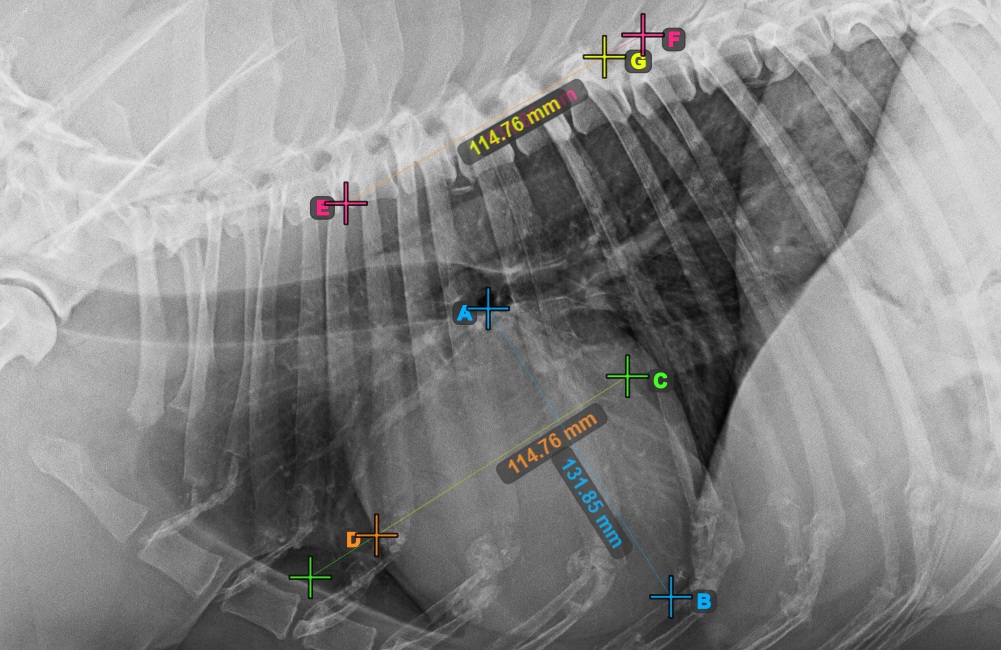

Start the measurement by marking the Bifurcatio tracheae, near the top of the heart.

The image below represents a typical placement of the Bifurcatio tracheae point.

Complete the long axis of the heart by marking the Apex point, near the bottom of the heart.

The image below represents a typical placement of the Apex point.

Continue the measurement by marking the widest right (cranial) point of the short axis of the heart.

The image below represents a typical placement of the most cranial point on the short axis of the heart.

Complete the short axis of the heart by marking the widest left (caudal) point.

The image below represents the typical placement of the most caudal point on the short axis of the heart.